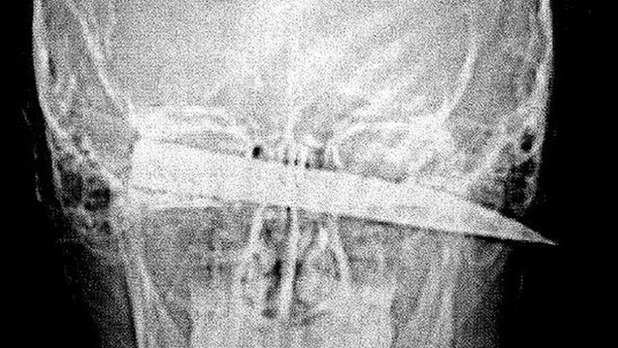

Prosecutor Alan Kent QC said the teenager was “lucky” to survive after the blade was completely buried in his head with the tip poking out the other side.